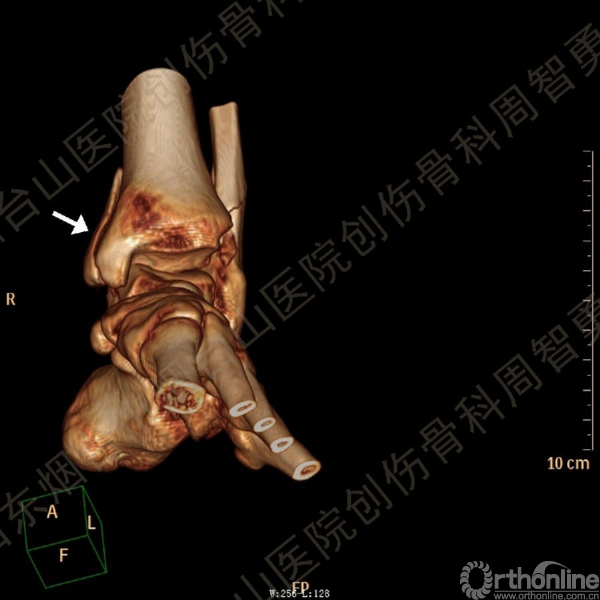

患者一般情况可,左踝关节肿胀,见皮下瘀斑,内、外、后侧有压痛,左踝关节主动运动受限,左足皮肤感觉、血供未见明显异常,左足趾各关节可主动运动。左踝关节正位X线片和CT重建示内踝内上方双层骨皮质影(图1a,c),CT示后侧骨折块分为后内侧骨折块和后外侧骨折块(图2a,b),后内侧骨折块累及内踝后丘,后丘骨折线呈冠状位(图2c),后内侧骨折块腹侧有向近端塌陷的小块骨软骨骨折块(图2d),CT也显示Chaput骨折块(图1c,2e)。

经典的后踝骨折发生于低能量旋转外力所致的踝关节骨折;标准pilon骨折见于高能量轴向暴力;而后侧pilon骨折是旋转外力和轴向暴力共同作用的结果,属于中等能量的损伤。踝关节骨折中的后踝骨折源自下胫腓后韧带的牵拉,骨折块位于后外侧,常为单一的三角形骨折块,大小从关节外片状骨折到累及胫骨远端关节面矢状径的40%(图4a)。后侧pilon骨折中的后侧骨折块较大,累及内踝后丘(三角韧带深层起点)在内的整个胫骨远端后侧,分为后内侧骨折块和后外侧骨折块,后内侧骨折块腹侧有向近端塌陷的骨软骨骨折块(图4b)。后侧pilon骨折中的内踝骨折线并不是水平位而是冠状位,可合并内踝前丘骨折。后侧pilon骨折踝关节正位X线片示特异性的内踝内上方双层骨皮质影(图1a,c)。这是由于后内侧骨折块的骨折线延伸到胫骨远端骨骺和干骺端的内侧骨皮质,其移位后的边缘成像所致。水平位CT显示后侧骨折块分为后内侧骨折块和后外侧骨折块,矢状位CT示后内侧骨折块腹侧有向近端塌陷的骨软骨骨折块。

↑ 图 2a

↑ 图 2b

↑ 图 2c

↑ 图 2d

↑ 图 2e

图 2 术前CT,显示后侧骨折块分为后内侧骨折块和后外侧骨折块(a,b),后内侧骨折块累及内踝后丘,后丘骨折线呈冠状位(c),箭头所示后内侧骨折块腹侧有向近端塌陷的小块骨软骨骨折块(d),Chaput骨折块(e)